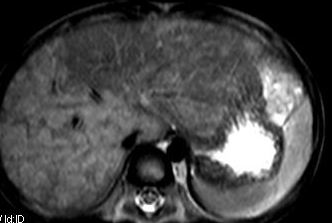

标题: V0176(MRI):小儿发热,肝脾大,肝内病变 [打印本页]

标题: V0176(MRI):小儿发热,肝脾大,肝内病变

5岁,2006年8月曾行阑尾炎手术,现发热半年